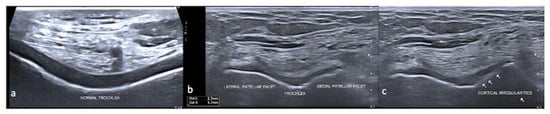

3.2. Ultrasound